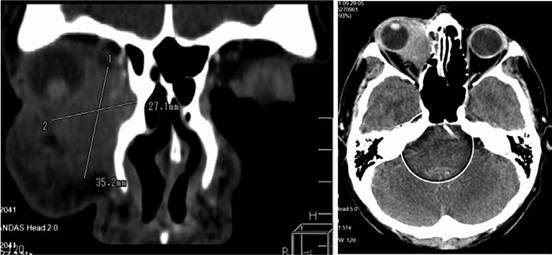

Paciente de sexo masculino de 61 años de edad, residente de Cochabamba, de ocupación agricultor referido de oftalmología por disminución de agudeza visual y conjuntivitis en ojo derecho. En el examen físico ocular, presentó pupila derecha midriática y reactiva, con edema corneal, tarsal y palpebral. La tomografía craneal y orbitario reflejó tumoración isodensa en cavidad orbitaria derecha adherida a pared medial erosionando la pared ósea y medial, globo ocular infiltrado en borde medial e inferior, además de compromiso de tejidos blandos superficiales (Figura 1). La biopsia de la región retro ocular reportó presencia de proliferación de células medianas a grandes con núcleo irregular, cromatina irregular, nucléolos con mitosis evidentes de 2-3 por campo, patrón difuso. Reporte de inmunohistoquímica compatible con Linfoma no Hodgkin de células T/NK (CD3+/CD56+). Los estudios laboratoriales reflejaron alteraciones en LDH: 880 u/L, serología viral Virus de hepatitis y VIH negativo, Citomegalovirus y Epstein Barr IgG positivo. Ecocardiograma conservado con FEVI 65 %.

La tomografía con contraste reportó seno maxilar izquierdo con lesión de densidad de partes blandas, medidas 103 x 96 x 69 mm, con realce heterogéneo ocupando la totalidad del seno con extensión a celdillas etmoidales que comprometía la luz de fosa nasal izquierda y disminución de luz nasofaringe del 50 %; además, se extiendía a cavidad orbitaria izquierda provocando desplazamiento de músculos mediales; con destrucción ósea, sin evidencia de adenopatías en otro sitio (Figura 5) sin infiltración a médula ósea. Ecocardiograma reportó insuficiencia mitral/tricúspidea leve con FEVI 57%.